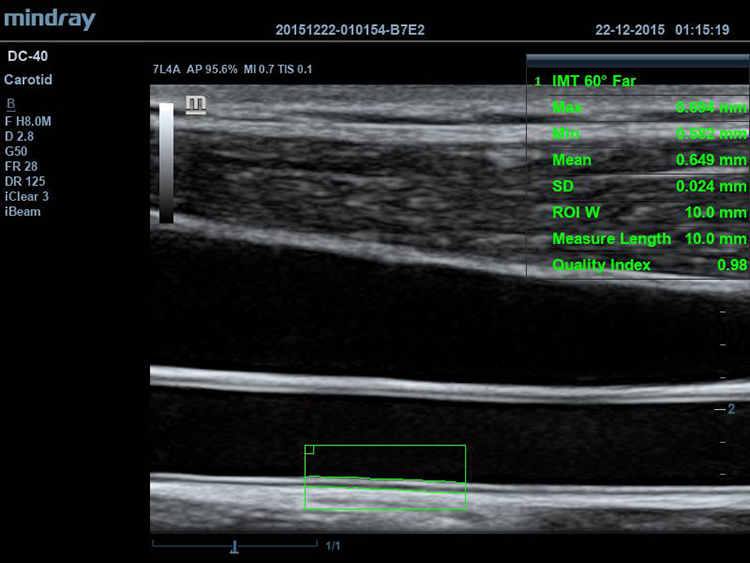

Авто IMT (толщина интима-медиа)

Автоматическое измерение толщины стенок артерии.

Линейный датчик Mindray 7L4A, (5.0/7.5/10.0MHz), 35 мм